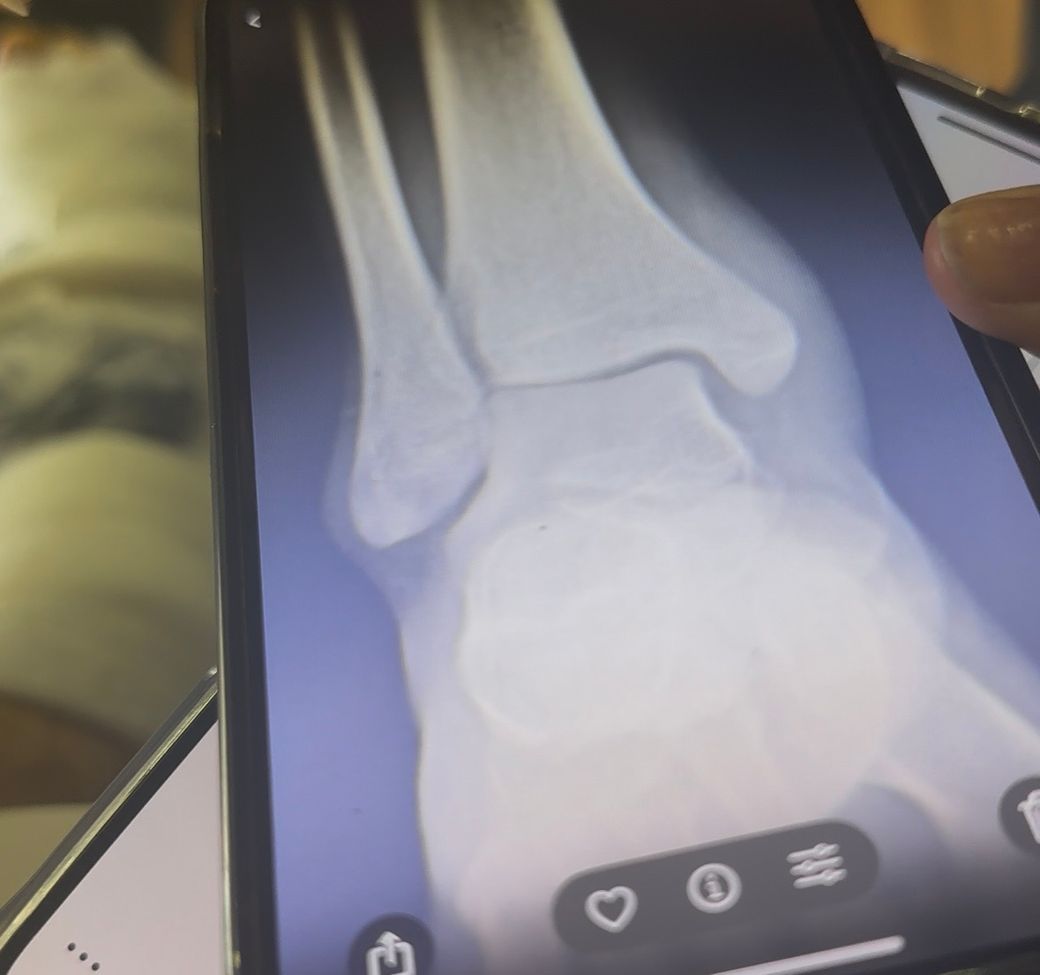

발목 골절 엑스레이사진 올립니다. 수술이 필요해보이는지요

발목이 골절되었습니다.

의사쌤들마다 의견이 나뉠수있지만 보셨을때 수술이 필요해보이는지 판단 부탁드립니다.

• 1번 째 사진

뼈 끝이 살짝 벌어지거나 어긋난 모습이 있어 "수술 가능성은 열려 있음"으로 보입니다.

그러나 전위가 아주 적고 관절면 정렬이 유지되면 "깁스로도 치료하는 경우가 있습니다."

CT(관절면) 확인이 중요하며 이를 기준으로 수술 여부가 결정됩니다.

"정렬 불량.관절면 깨짐.인대 불안정"이 있으면 수술, 아니면 보존적 치료가 가능합니다.